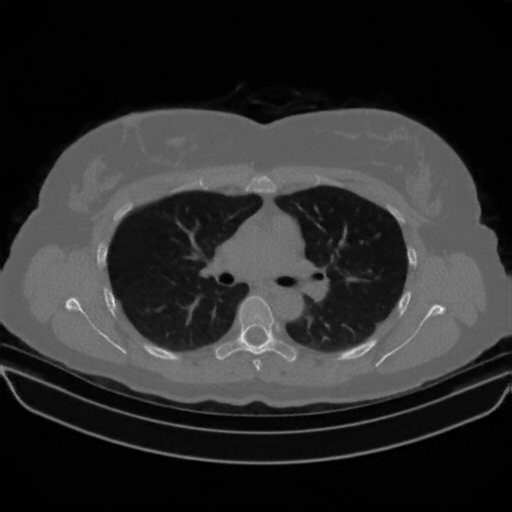

Targeted Slice 70 - Network-Normalized Analysis (Generated vs Real Venous)

0.885

SSIM Score

0.092

RMSE

0.040

MAE

Average Network-Normalized Metrics Across All Slices (170 slices) - Generated vs Real Venous

0.886

SSIM Score (Avg)

0.097

RMSE (Avg)

0.041

MAE (Avg)

Image Grid

4Γ—3 grid: Rows show different image types (Original NATIVE, Reconstructed NATIVE, Original VENOUS, Generated VENOUS), Columns show windowing techniques (No Window, Lung Window, Mediastinum Window)

Original VENOUS CT scan

Mediastinum window (WL 40, WW 400 β†’ Low βˆ’160, High +240)